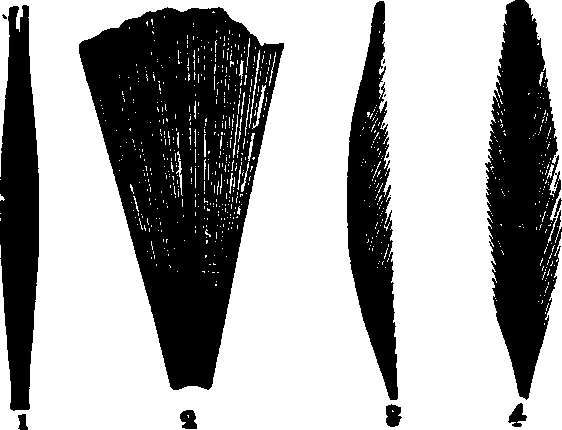

Fig. 20. 1. A

spindle-shaped muscle, with tendinous terminations. 2. Fan-shaped muscle.

3. Penniform muscle. 4. Bipenniform muscle.